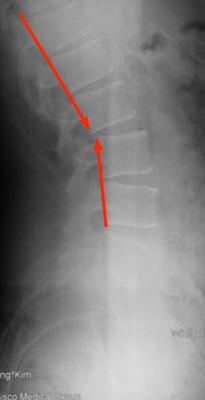

Let's start with the x-rays. There are three significant findings. Firstly on the lateral lumbar (is an extension view?) there a sharp posterior angulation of L2 on L3 which is indeed where the superior cluneal nerves emanate from.

Secondly, on the lateral lumbar MRI there appears to be a disc bulge at L3-L4 which may contribute.